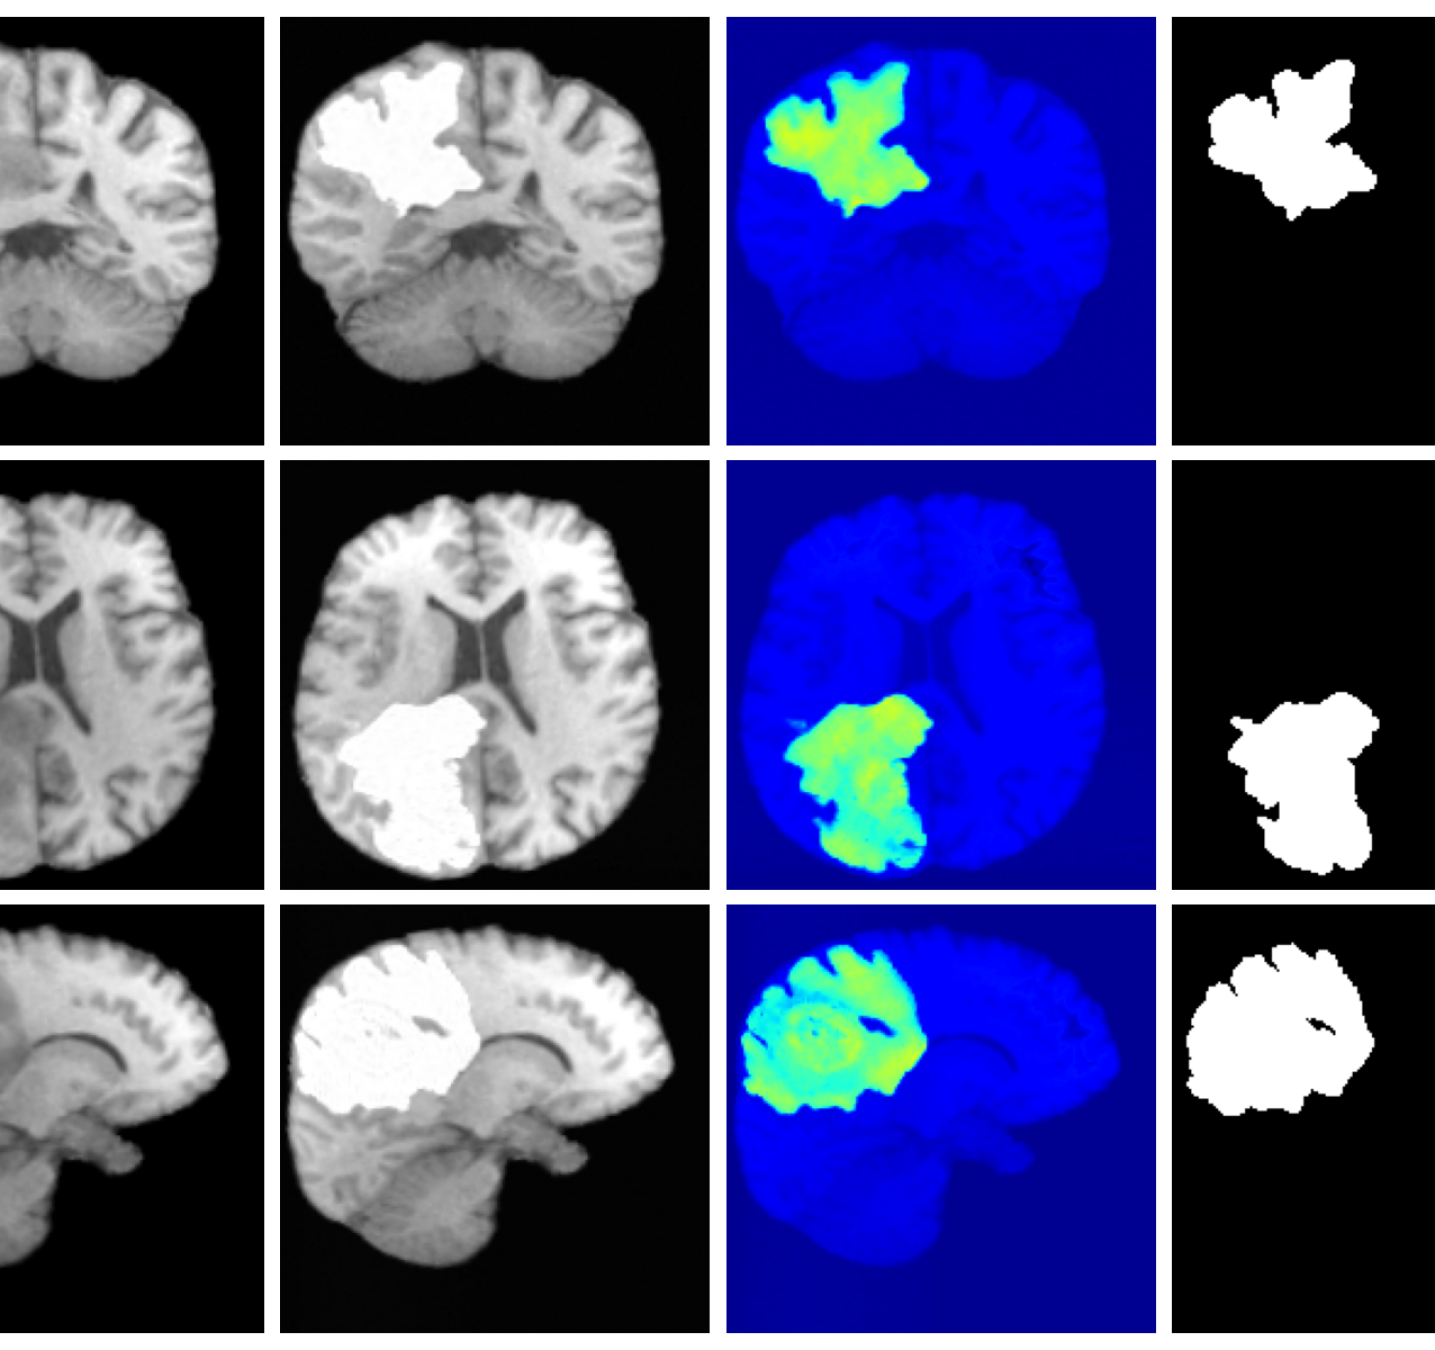

Figure 3 (additional examples in Appendix A.9) shows that SynthSR preserves healthy tissue but struggles with large lesions, while DDPM-2D and DDPM-3D, despite producing high-contrast anomaly maps, generate unrealistic homogeneous inpainting, consistent with their lower performance in Table 3. In contrast, our method yields the most anatomically plausible inpainted regions, although anomaly maps appear subtle due to low contrast between lesions and healthy tissue.

A.9 Additional qualitative inpainting results

Additional qualitative results for the ATLAS and BraTS datasets are given in Figures 12 and 13, respectively.